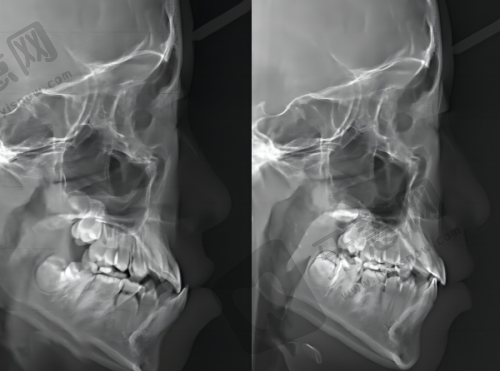

医院简介:二级口腔专科医院,是武汉少有的“复杂正畸重点机构”;正畸科由原国有三等甲医院正畸主事领衔,团队擅长处理青少年龅牙、地包天、开颌等复杂错颌畸形;医院配备进口正畸设备,能实现精细的牙齿移动控制,技术实力获行业认可。

特色项目:青少年复杂错颌畸形矫正(如骨性地包天早期干预)、自锁托槽矫正(缩短1/3矫正周期)、个性化隐形矫正(根据孩子牙弓形态定制);针对青少年敏感心理,设置“一对一私密诊室”,避免孩子因围观产生紧张感。